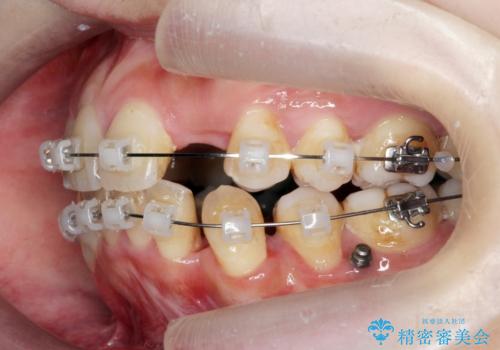

重度のがたつき 矯正治療+セラミック治療で綺麗な歯並びに 矯正専門では難しい治療

- 歯並びを気にして来院。

乳歯が残存しており、また左上の犬歯もずれて生えてきていました。

右上の前歯も細長い特殊な形をしていました。(矮小歯といいます)

矯正治療で歯並びを治した後、乳歯を抜いたところにブリッジを入れています。

左上の奥歯はすれ違っていたためそのかみ合わせも整えています。